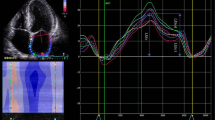

Global longitudinal 2D LA strain was analyzed by the speckle tracking technique using GE EchoPAC software. The images were acquired according to the recommendations given by expert consensus statement published in the European Journal of Echocardiography [17]. For analysis we used four-chamber and two chamber apical view images of LA carefully avoiding foreshortening. The focus was set to the level of mid-LA to optimize the image quality. Sector depth and width was adjusted to include as little as possible outside the region of interest. Three consecutive heart cycles were recorded during a single breath hold using a frame rate of > 80 frames/second for offline analysis. The endocardial border of LA was manually traced and a region of interest was manually adjusted to include the entire LA wall thickness. The software selected stable speckles within the LA wall and tracked these speckles frame-by-frame throughout the cardiac cycle. The entire LA tracking was then divided into 6 segments by the software and tracking quality for each segment was provided. If the tracking was not acceptable, endocardial borders were readjusted until better tracking was achieved. Then, we set the starting point of strain analysis as P-wave onset instead the software preset R-wave peak. The automated software then generated traces depicting the regional longitudinal strain for each segment and calculated global longitudinal strain. Using P wave onset as starting enabled us to define first negative peak, which occurred at maximal LA contraction and represented its contractile function (contractile strain), first positive peak, which occurred at mitral valve opening and represented LA conduit function (conduit strain), and the difference of these peaks, which represented reservoir function (reservoir strain). The values were averaged for all 12 LA segments - 6 in apical four chamber view and 6 in apical two chamber view. LA strain image from four-chamber apical view is shown in Fig. 1. Analogous measurements were performed from apical two-chamber views.

2D LA strain image from four-chamber apical view. Setting the starting point of strain analysis at the beginning of the p wave on the ECG allowed us to define first negative peak, first positive peak and the difference of these peaks which corresponded to atrial contractile strain, conduit strain and reservoir strain respectively